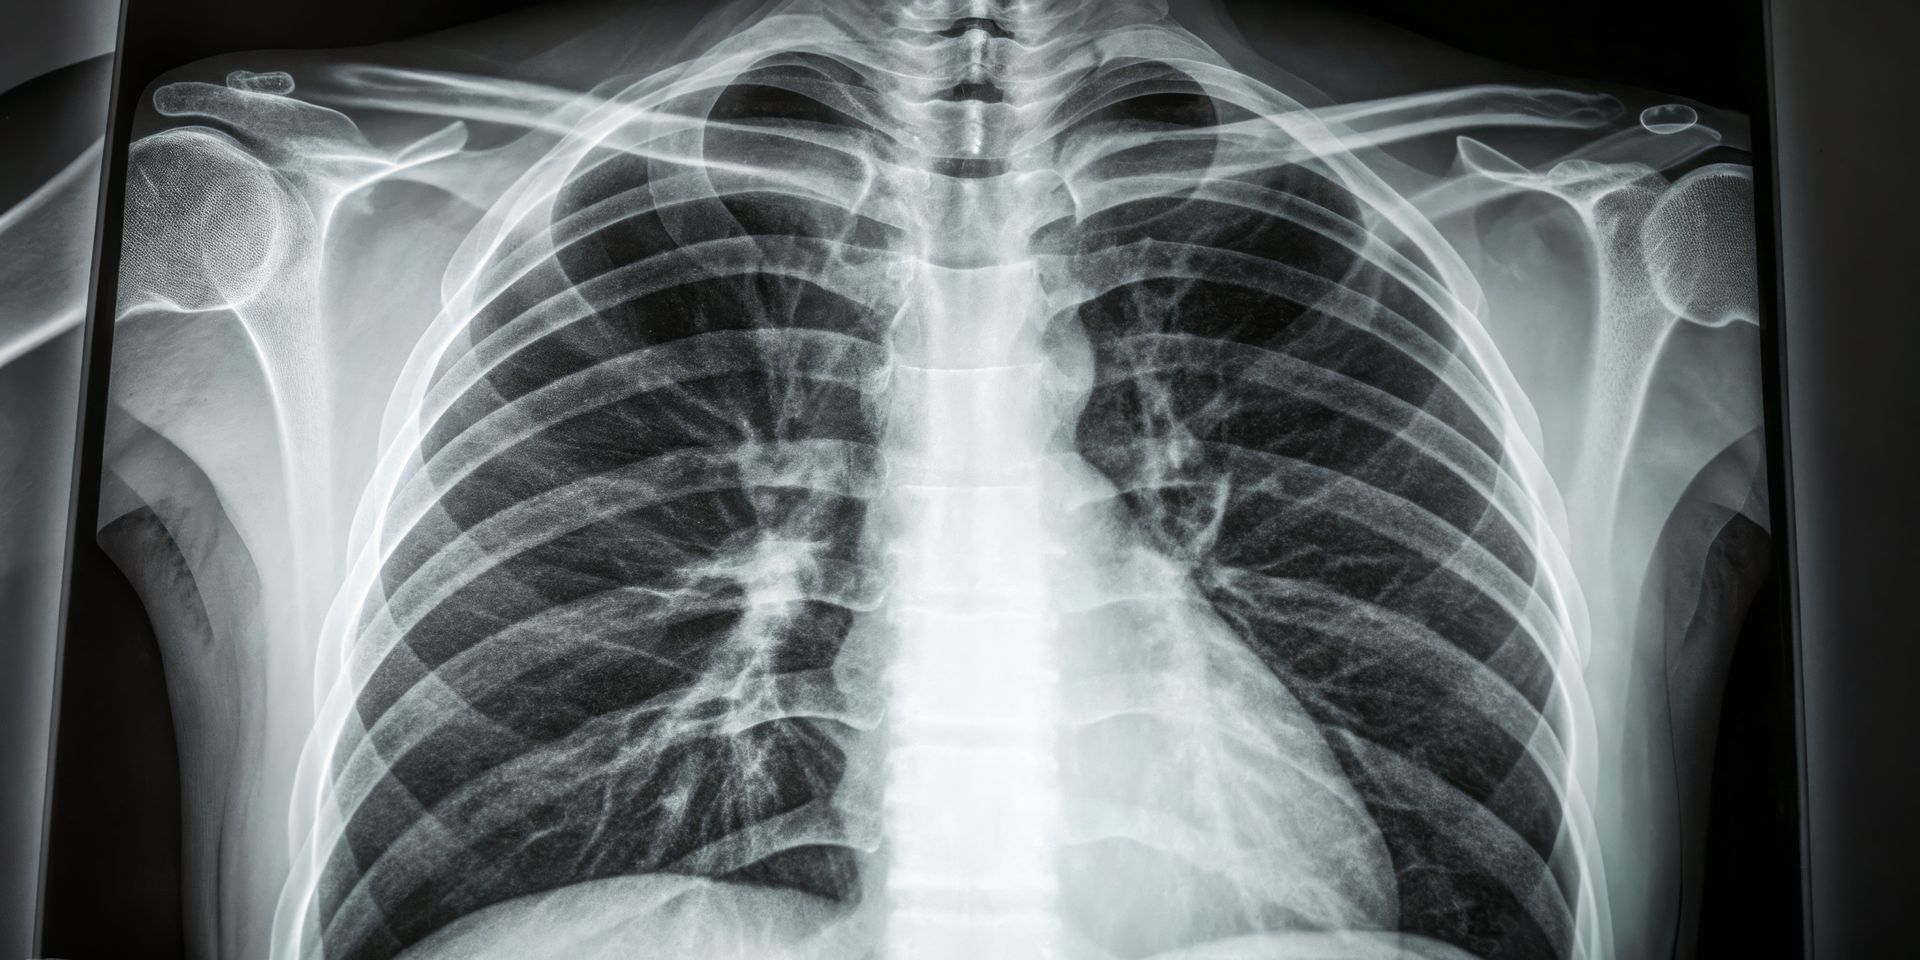

A segmentectomia robótica é um tipo de cirurgia minimamente invasiva que remove apenas um segmento do pulmão, em vez de um lobo inteiro. Indicado principalmente para tumores pulmonar periféricos com até 2 cm, esse procedimento preserva mais tecido saudável e oferece recuperação mais rápida.

A segmentectomia é uma cirurgia pulmonar que

remove apenas uma parte específica de um lobo do pulmão — chamada de segmento. Ao contrário da lobectomia, que retira o lobo inteiro, essa técnica busca

preservar o máximo possível do tecido pulmonar saudável, sendo especialmente indicada para casos de câncer em estágio inicial. O procedimento segue critérios rigorosos de oncologia, garantindo margens adequadas e remoção de linfonodos, tudo isso com uma abordagem minimamente invasiva.